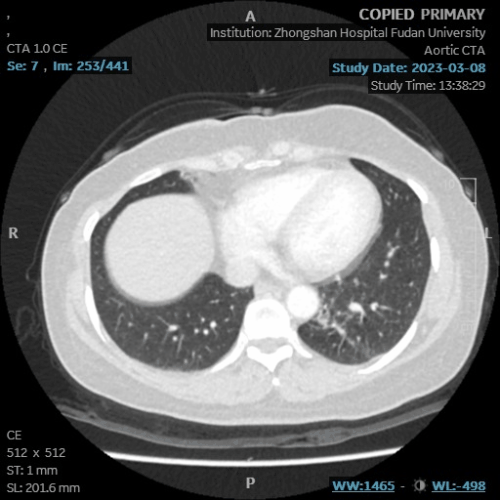

老年女性,体检发现左下肺实性阴影,伴多发囊性改变及渗出,体检报告疑似肺隔离征。

来院就诊,即行主动脉CTA见左下肺病灶处理由主动脉供血分支,

凭此典型征象可确诊为肺隔离征,本例影像较为典型,一般不会误诊为肺癌。